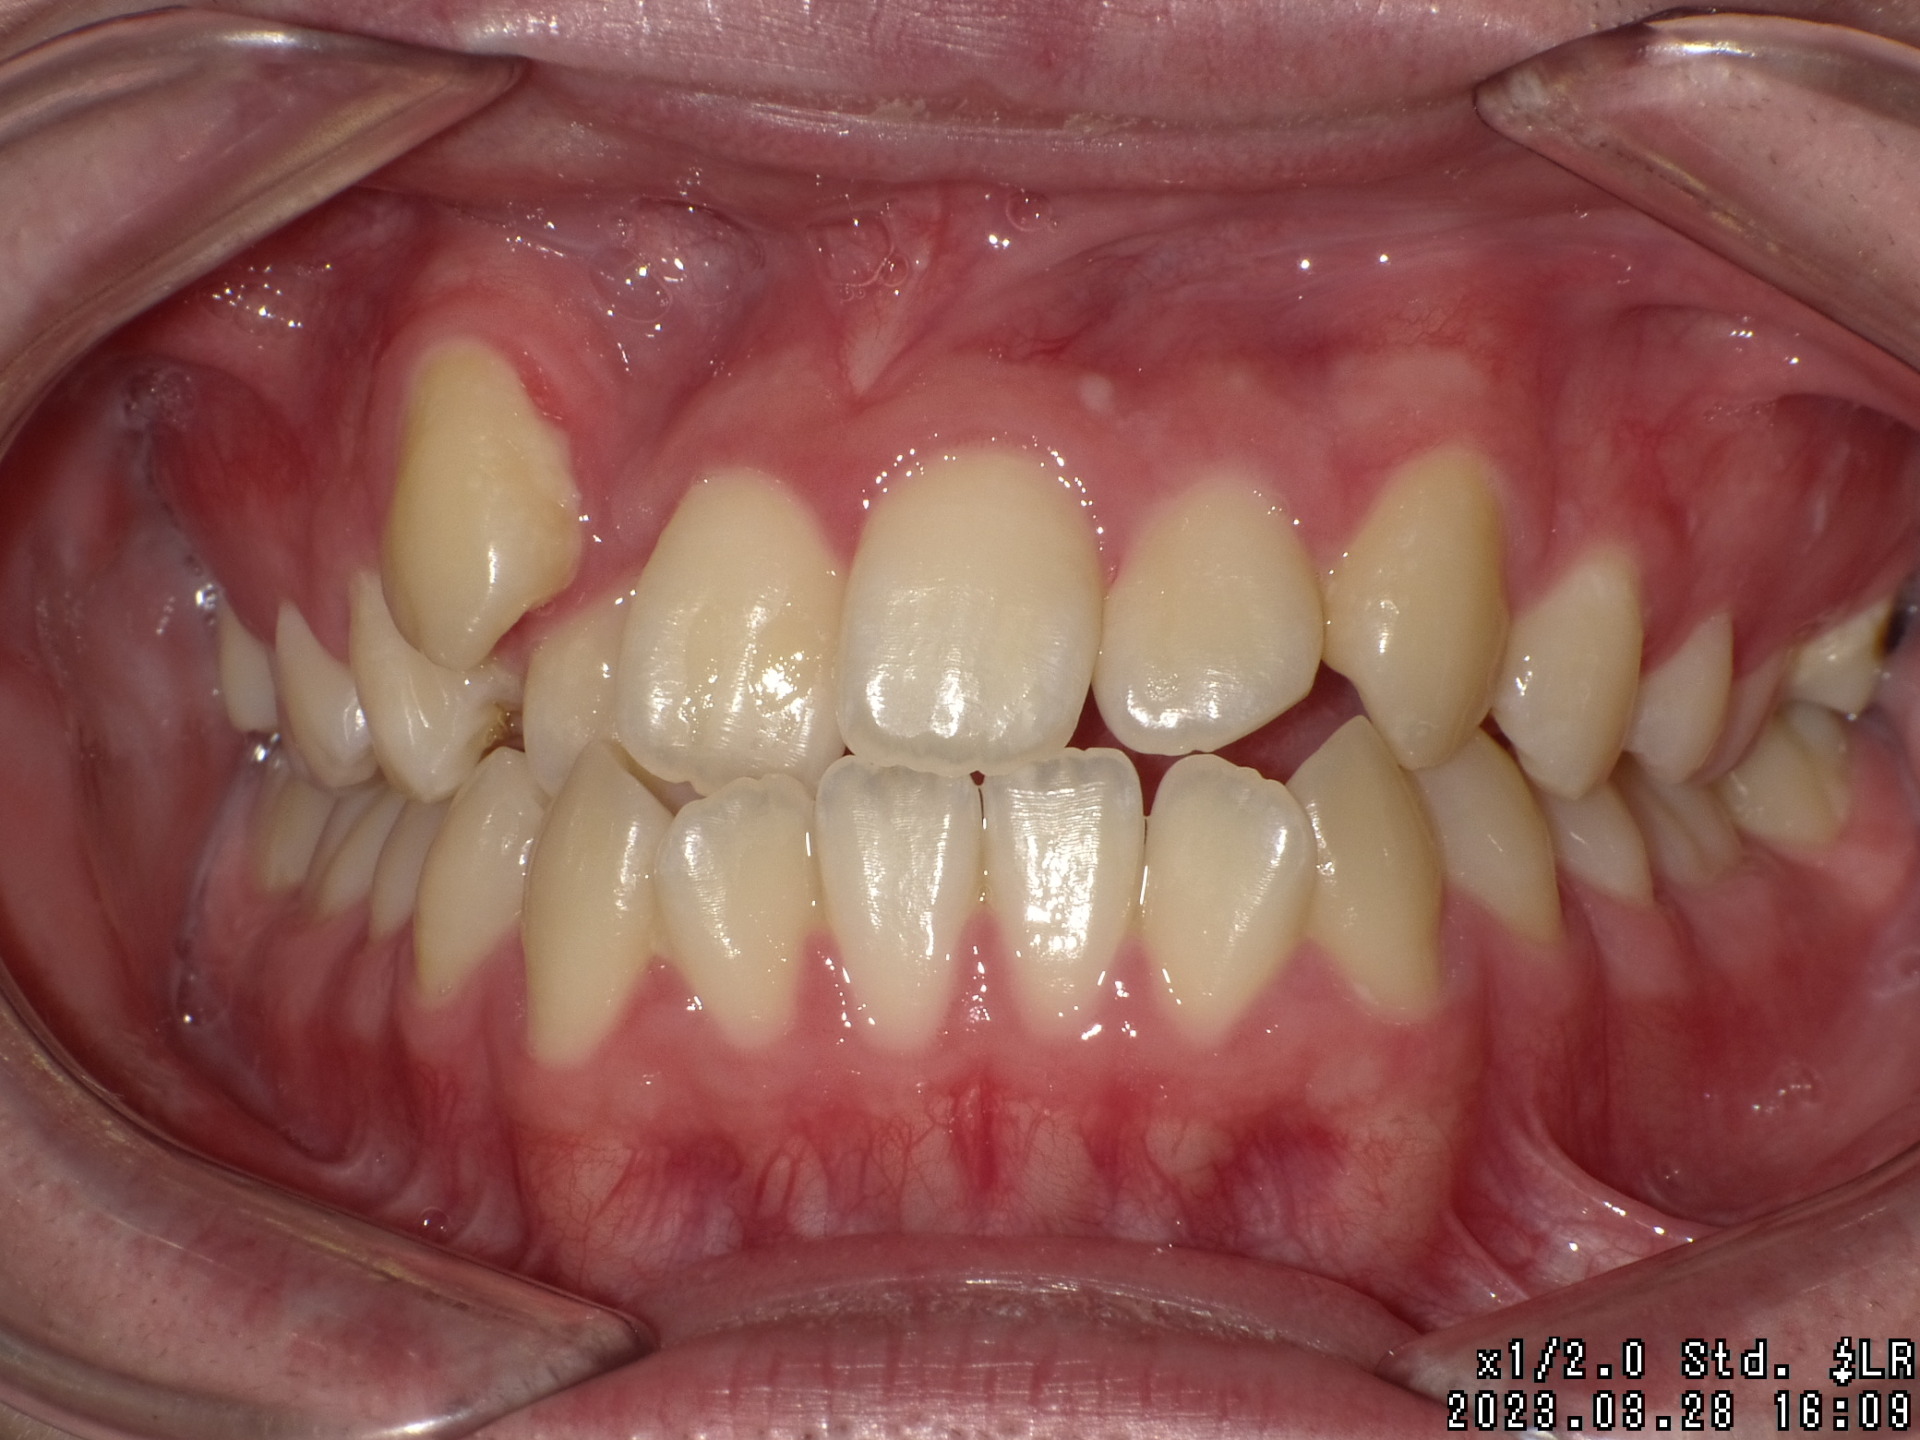

Before

| 症状 | 右上八重歯 上顎正中の著しいずれ |